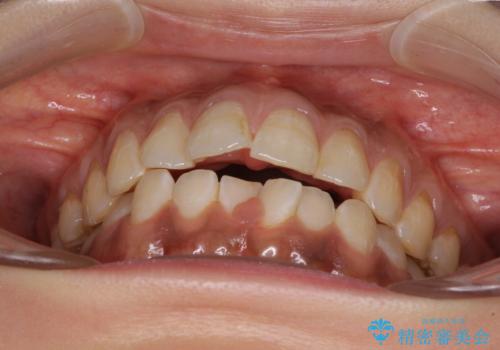

- 前歯のデコボコと上下前歯の隙間を気にして来院された患者様です。

下顎前歯はデコボコのため、歯肉が腫れやすくなっていました。

また、舌突出癖のため、上下前歯の間に隙間ができてしまい、上顎前歯が前方に傾斜している状態でした。